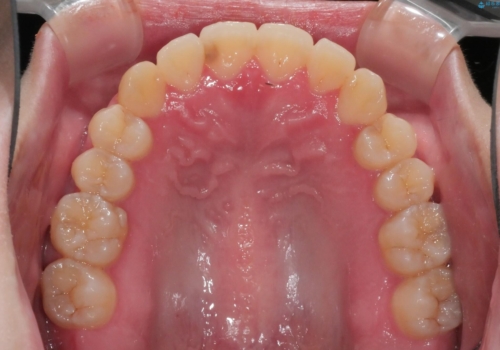

- 非抜歯、インビザライン治療希望の患者様です。

右の犬歯が八重歯になっており、通常であれば抜歯を選択する可能性が高くなりますが、

マイクロインプラントと呼ばれる骨に打ち込むネジを使用し、非抜歯での治療計画を立てました。

マイクロインプラントを使用することで非抜歯での治療が可能となりました。

マイクロインプラントを使用せずに無理に非抜歯治療を行った場合、

治療後に出っ歯になってしまうなどの問題が起きる可能性が高いです。